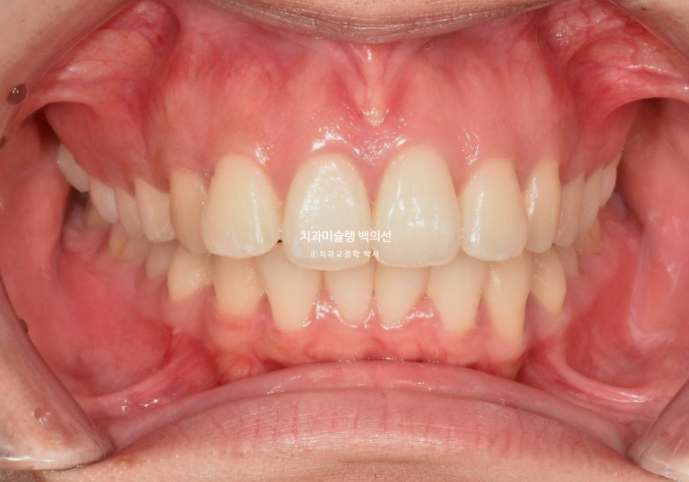

25.09

블랙트라이앵글 사이즈는 많이 줄였고 중심선은 잘 맞습니다.

어금니 교합은 물샐틈 없는 1급관계입니다.